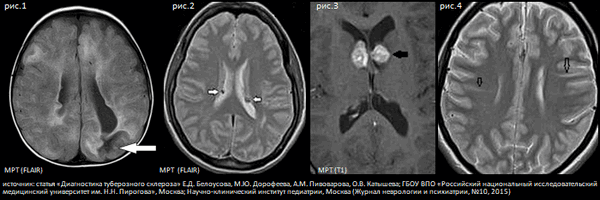

Описанная выше симптоматика ТС обусловлена структурными изменениями мозга, которые выявляются при нейро-радиологическом исследовании. К ним относятся корковые и подкорковые туберы [см. рис.1] (зоны дисплазии, в которых нарушено нормальное линейное строение коры и содержатся аномально большие клетки или «клетки-баллоны». Туберы обнаруживаются у 95 - 100% пациентов. Часто именно туберы являются причиной эпилепсии. Субэпендимальные узлы (см. рис.2) встречаются у 80% пациентов, по морфологическому строению они напоминают туберы и имеют характерную нейро-радиологическую картину. Одним из наиболее серьезных и жизнеугрожающих симптомов ТС являются субэпендимальные гигантоклеточные астроцитомы [см. рис.3] (СЭГА), которые встречаются примерно у 20% пациентов. Считается, что опухоль развивается из субэпендимальных узлов в первые 2 десятилетия жизни, но иногда она может обнаруживаться и у новорожденного ребенка. Как правило, СЭГА располагаются около отверстия Монро, растут медленно, но при росте вызывают развитие прогрессирующей гидроцефалии (проявляется рвотой, головной болью, снижением остроты зрения вплоть до слепоты, развитием спастического тетрапареза). Если пациент не будет прооперирован или не будет получать ингибитор m-TOR эверолимус, прогрессирующая гидроцефалия может привести к летальному исходу. Кроме того, у пациентов с ТС часто выявляются радиальные полосы белого вещества - радиальные миграционные тракты (см. рис.4), которые являются следствием нарушения нейрональной миграции, и кисты у задних рогов боковых желудочков. Могут встречаться и другие аномалии строения коры (фокальные дисплазии, шизэнцефалия, гетеротопии, частичная агенезия мозолистого тела).